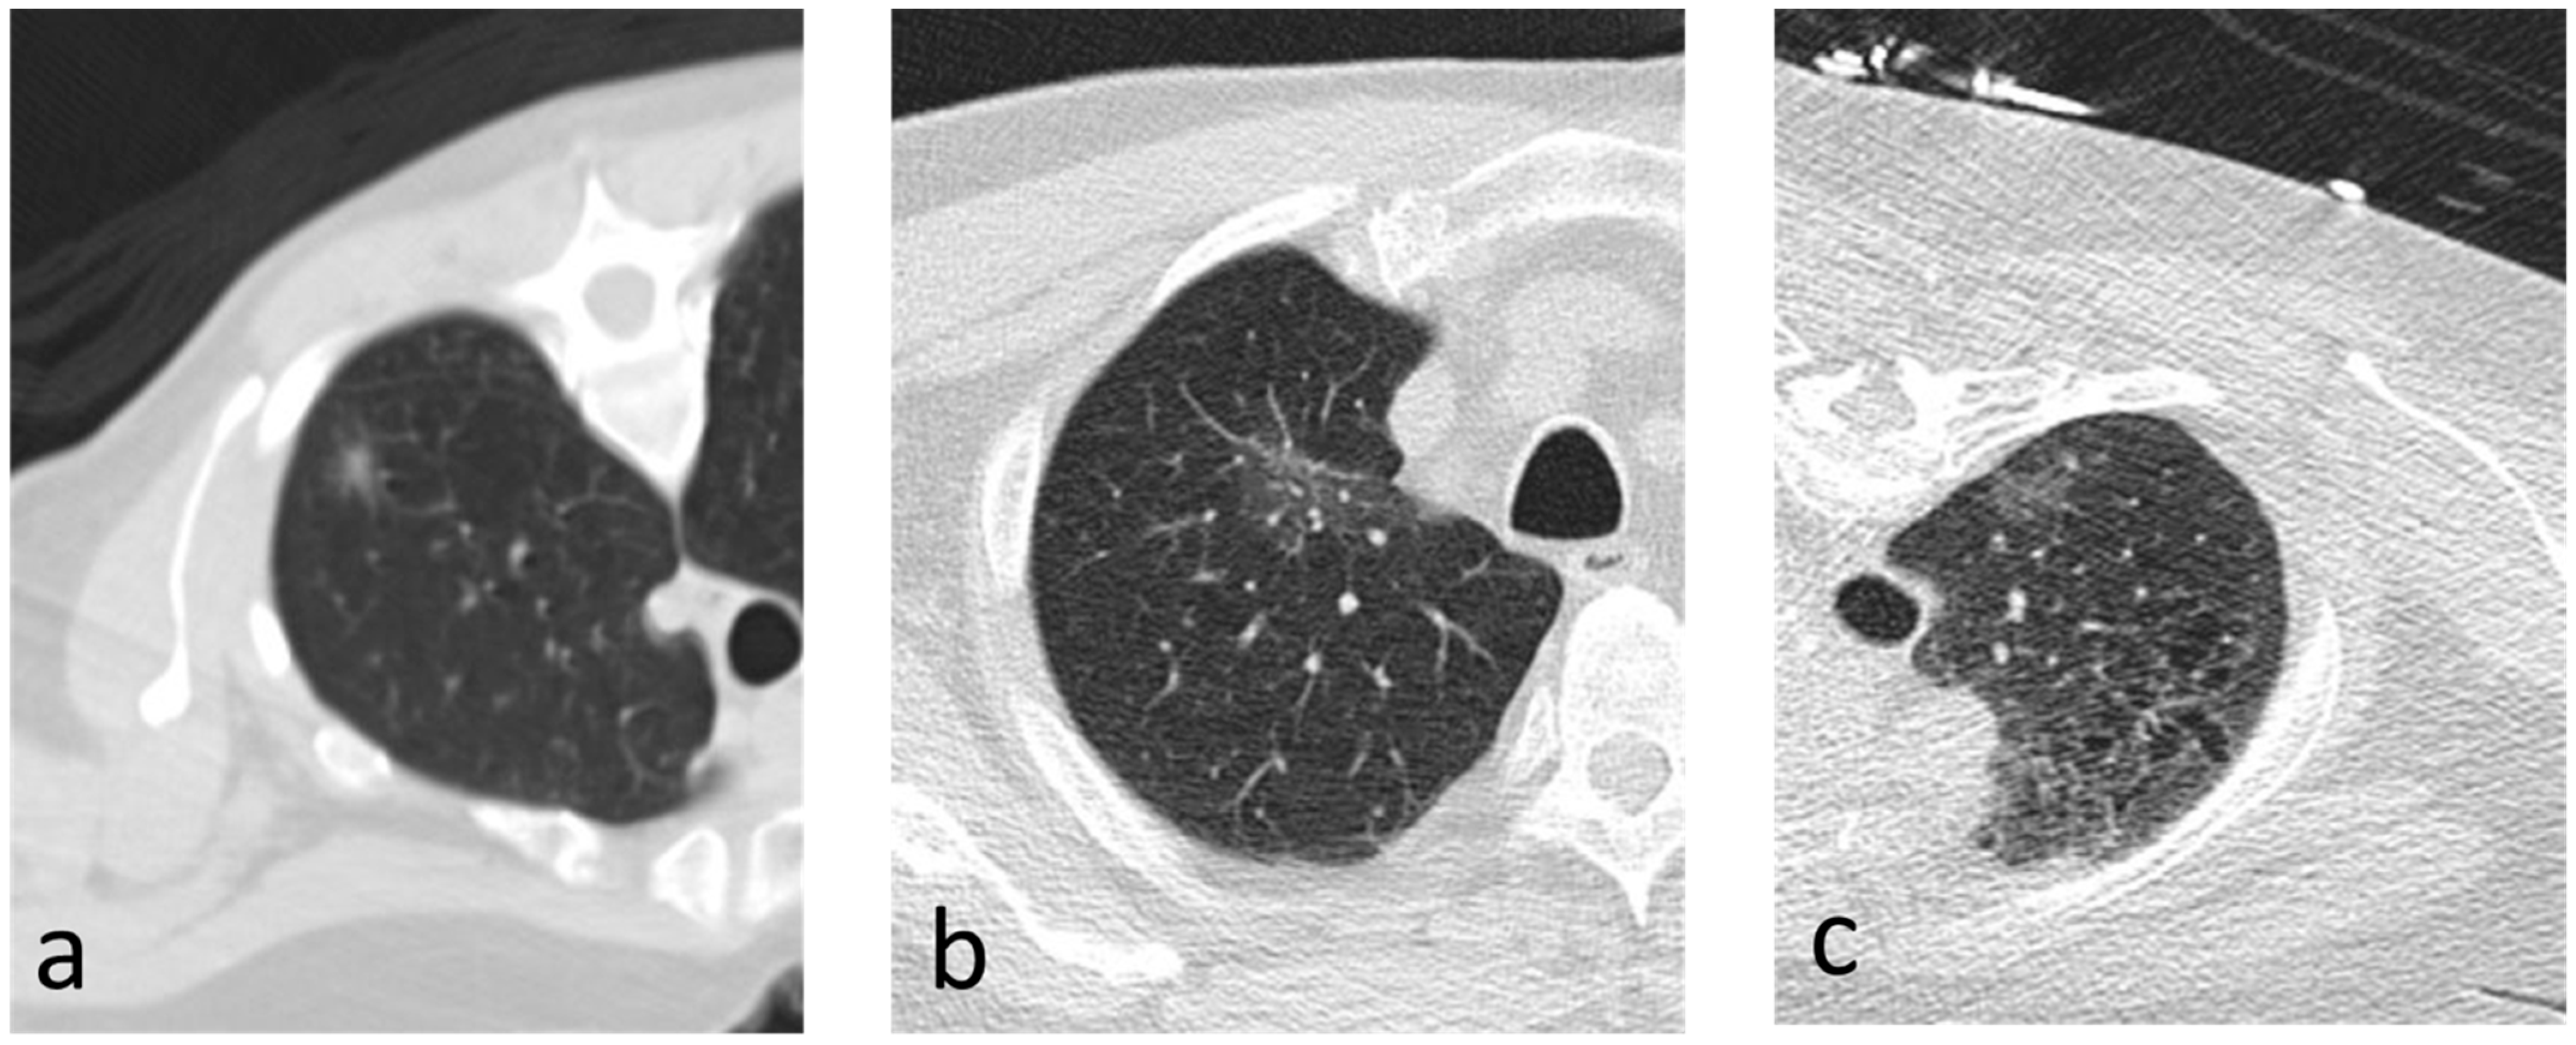

Predicting Invasiveness in Lepidic Pattern Adenocarcinoma of Lung: Analysis of Visual Semantic and Radiomic Features

3.1. Visual Read Variables

3.2. Radiomic Variables